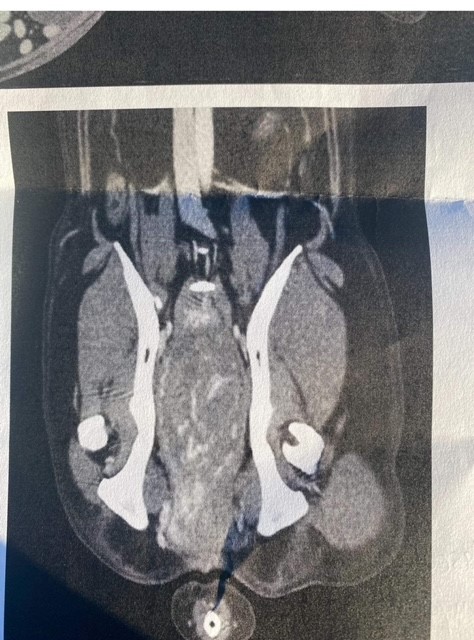

Rosie has been a client of mine for some time. She is the first English Setter I have worked with and has taught me a huge amount about breed. Around late February last year (2023) after a series of UTI’s her guardian and I started noticing changes in both Rosie’s conformation and behaviour. Diligently her guardian sought further veterinary advice and in March our worse fears were confirmed. Rosie had a large mass that was blocking both her bladder and bowel.

The removal of this mass was not straight forward, the mass ruptured during surgery, causing a large bleed, resulting in Rosie becoming critically ill in the days that followed. During this time a heart murmur developed and her guardian was advised to manage her expectations about whether Rosie would be returning home.

“Where to start with Laura? She just brings a wonderful aura into my home and leaves us with a well needed sense of calm.. I first met Laura after recommendation when Rosie was injured in a dog attack with a corkscrew spine injury. At first Rosie was a bit reluctant to allow a stranger to touch her, as the human in charge of the dog that attacked her leapt towards her to get his dog off of her, leaving her wary of close contact of strangers. Laura worked sensitively in the first session to build trust, truly working with Rosie rather than ‘on’ her. I noticed an improvement straight away, and on her second session Rosie chose to come and lay by Laura ready, as soon as she entered the room. She recovered better than vets expected and went back to agility and dog shows. Fast forward to March 2023. After a period of uti’s that the vet could not find a cause, after yet another check for a pyometra a mass was seen on a scan and she was referred a specialist. She ended up with emergency surgery with a tumour in her pelvis that had grown and was now blocking both bowel and bladder. After five days, nearly losing her, I bought home a broken dog. But Laura was there straight away to aid her recovery again. No one in breed showing thought she would ever be able to return to the show ring and advised me to retire her. But in the following September, at her first championship show, (Richmond) she not only came first in her class , but gained her Stud book number, qualifying her for life for Crufts. She has also made a return to agility and we hope to venture into some competition this year. I feel sure none of this would have been possible without Laura’s help.”Where to start with Laura? She just brings a wonderful aura into my home and leaves us with a well needed sense of calm.. I first met Laura after recommendation when Rosie was injured in a dog attack with a corkscrew spine injury. At first Rosie was a bit reluctant to allow a stranger to touch her, as the human in charge of the dog that attacked her leapt towards her to get his dog off of her, leaving her wary of close contact of strangers. Laura worked sensitively in the first session to build trust, truly working with Rosie rather than ‘on’ her. I noticed an improvement straight away, and on her second session Rosie chose to come and lay by Laura ready, as soon as she entered the room. She recovered better than vets expected and went back to agility and dog shows. Fast forward to March 2023. After a period of uti’s that the vet could not find a cause, after yet another check for a pyometra a mass was seen on a scan and she was referred a specialist. She ended up with emergency surgery with a tumour in her pelvis that had grown and was now blocking both bowel and bladder. After five days, nearly losing her, I bought home a broken dog. But Laura was there straight away to aid her recovery again. No one in breed showing thought she would ever be able to return to the show ring and advised me to retire her. But in the following September, at her first championship show, (Richmond) she not only came first in her class , but gained her Stud book number, qualifying her for life for Crufts. She has also made a return to agility and we hope to venture into some competition this year. I feel sure none of this would have been possible without Laura’s help.”